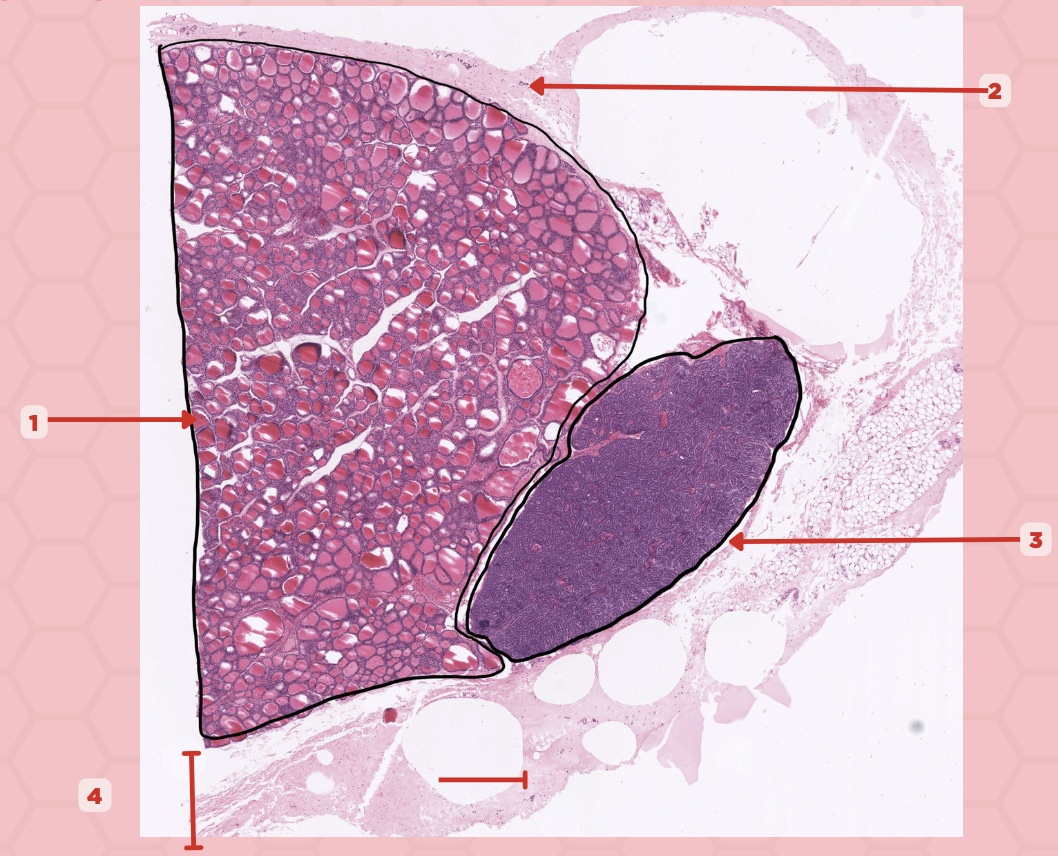

True

True or False: These (#1) are extracellular/calcified bodies that increase with age.

Corpora Arenacea

Identify the structure labeled as 1.